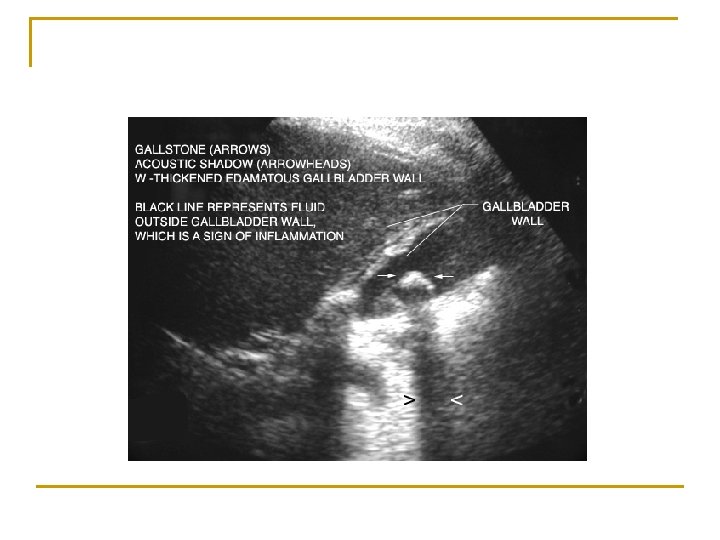

n n n Tanı: Tanı USG (safra kesesi duvarında >2 mm’lik kalınlaşma, perikolesistik sıvı, intramural gaz, kanallarda dilatasyon; sonografik Murphy pozitifliği) HIDA sintigrafisi, BT Tedavi: Tedavi I. V sıvı + GİS istirahati + parenteral analjezik + antibiyoterapi (komplike olgular, ağır seyir, immünsüpresyon, yaşlı, sarılık) + kolesistektomi/kolesistotomi Komplikasyon (%10 -15): hepatik, karın içi apse, safra kesesi nekrozu, gangreni, perforasyonu